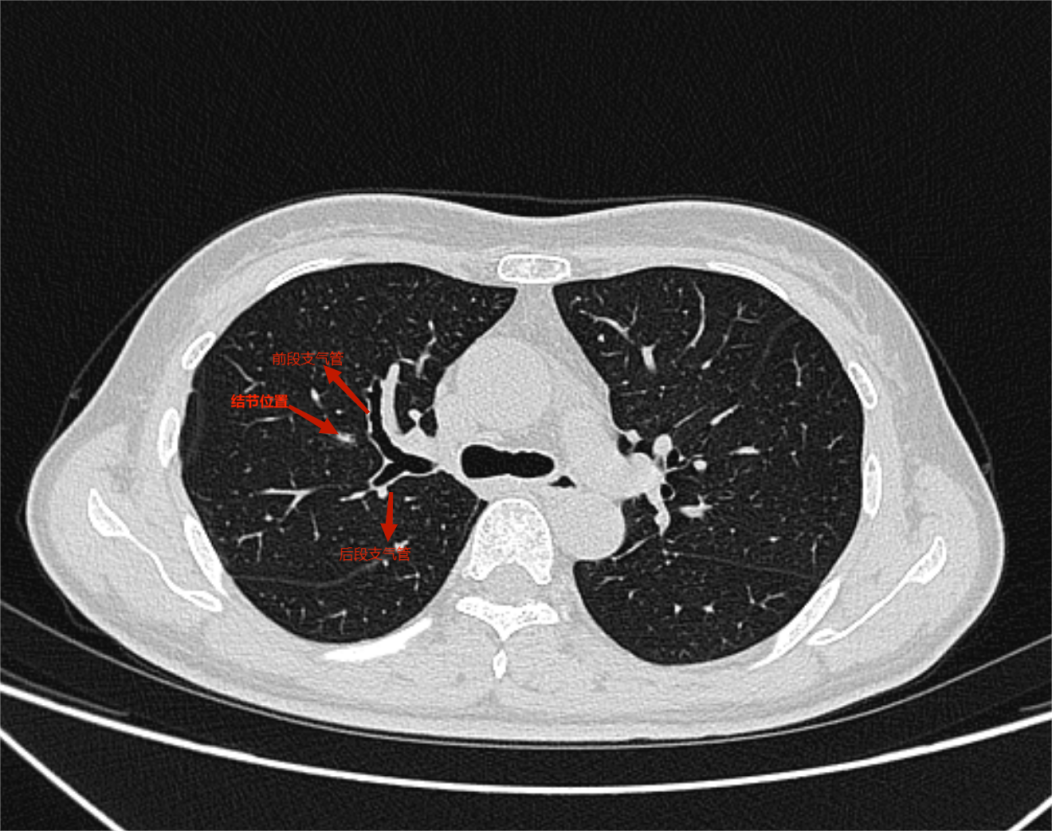

经随访观察半年后,在复查时发现结节增大至8mm,考虑早期恶性肿瘤可能性大,胸外科侯向生主任团队在详细阅读胸部CT后,确定结节位置及靶肺支气管、肺动、静脉情况,发现其结节位于右肺上叶前段与后段交接处,位置较深。结合病人意愿和病情现况,侯向生主任团队在保留肺功能和完整切除肿瘤间抉择出最优手术方案--右肺上叶前段切除。

(术前胸部ct)

术中离断前段气管、血管后应用膨胀萎陷法确定段间平面位置,将前段完整切除,并极大保留剩余肺组织,手术顺利完成。